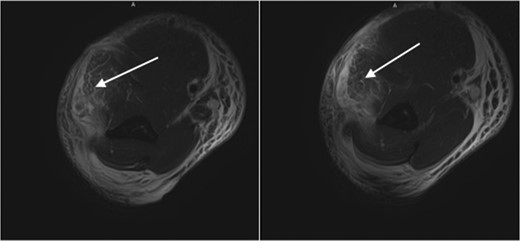

A previously healthy male in his 30s presented to the emergency department with a 2-day history of pain and swelling in his right upper extremity after striking a heavy bag with an uppercut punch. At the time of event, the patient felt a sudden sharp pain radiating from the wrist to the elbow, which eventually localized to the elbow. Over the next 2 days, the patient gradually developed swelling and diffuse erythema from the proximal aspect of the right arm to the wrist, tension, and decreased elbow, wrist and finger mobility. He reported a history of compartment syndrome requiring fasciotomy in his right distal arm and proximal forearm due to an automobile accident-induced crush injury 10 years prior. On exam, he was tender to palpation, weak to grip, but had intact sensation and vasculature. Initially, cellulitis was suspected, partly because of the appearance of his extremity and an unlikely traumatic mechanism for ACS. Radiographs were unremarkable for fractures. Magnetic resonance imaging (MRI) revealed extensive edema in the proximal brachioradialis muscle and extensor carpi radialis longus muscle, as well as increased signal in the extensor musculature at the dorsal aspect of the arm, but no fracture or tendinous, ligamentous or muscular tear (Fig. 1). Ultrasound showed a non-occlusive thrombus in the right axillary and brachial veins, for which the patient was eventually started on anticoagulation. All initial labs were unremarkable except the CPK of 973 and the patient was subsequently admitted.

White arrows: high-grade muscle strain of the muscles the dorsal compartment with extensive soft tissue edema throughout the arm.